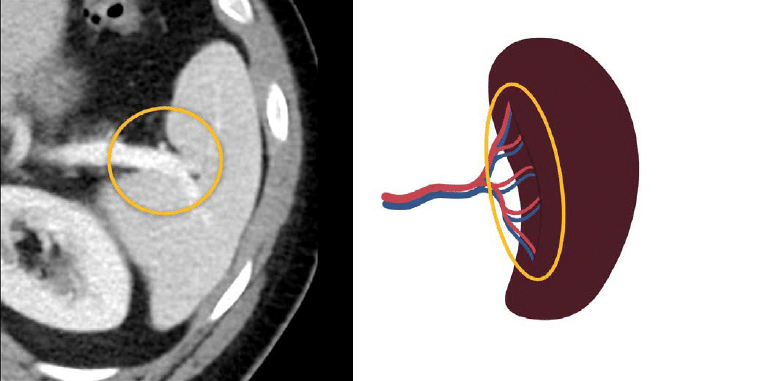

Accessory spleens are small, additional spleens that can develop alongside the primary spleen. They contribute to the body’s immune response and can be found in various locations within the abdominal cavity. Understanding their function and significance can aid in diagnosing certain medical conditions and enhance treatment strategies.

What are accessory spleens?

Accessory spleens are small, additional spleens that can develop in the body, typically near the primary spleen.

Do accessory spleens serve any purpose?

Yes, they play a role in immune function and can help with blood filtration, similar to the primary spleen.